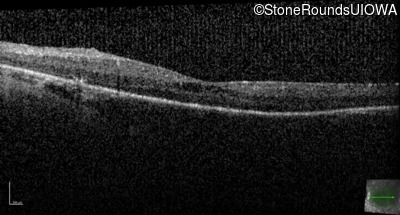

Optical Coherence Tomography - Left - 20/50

Exemplar / OCT Stack